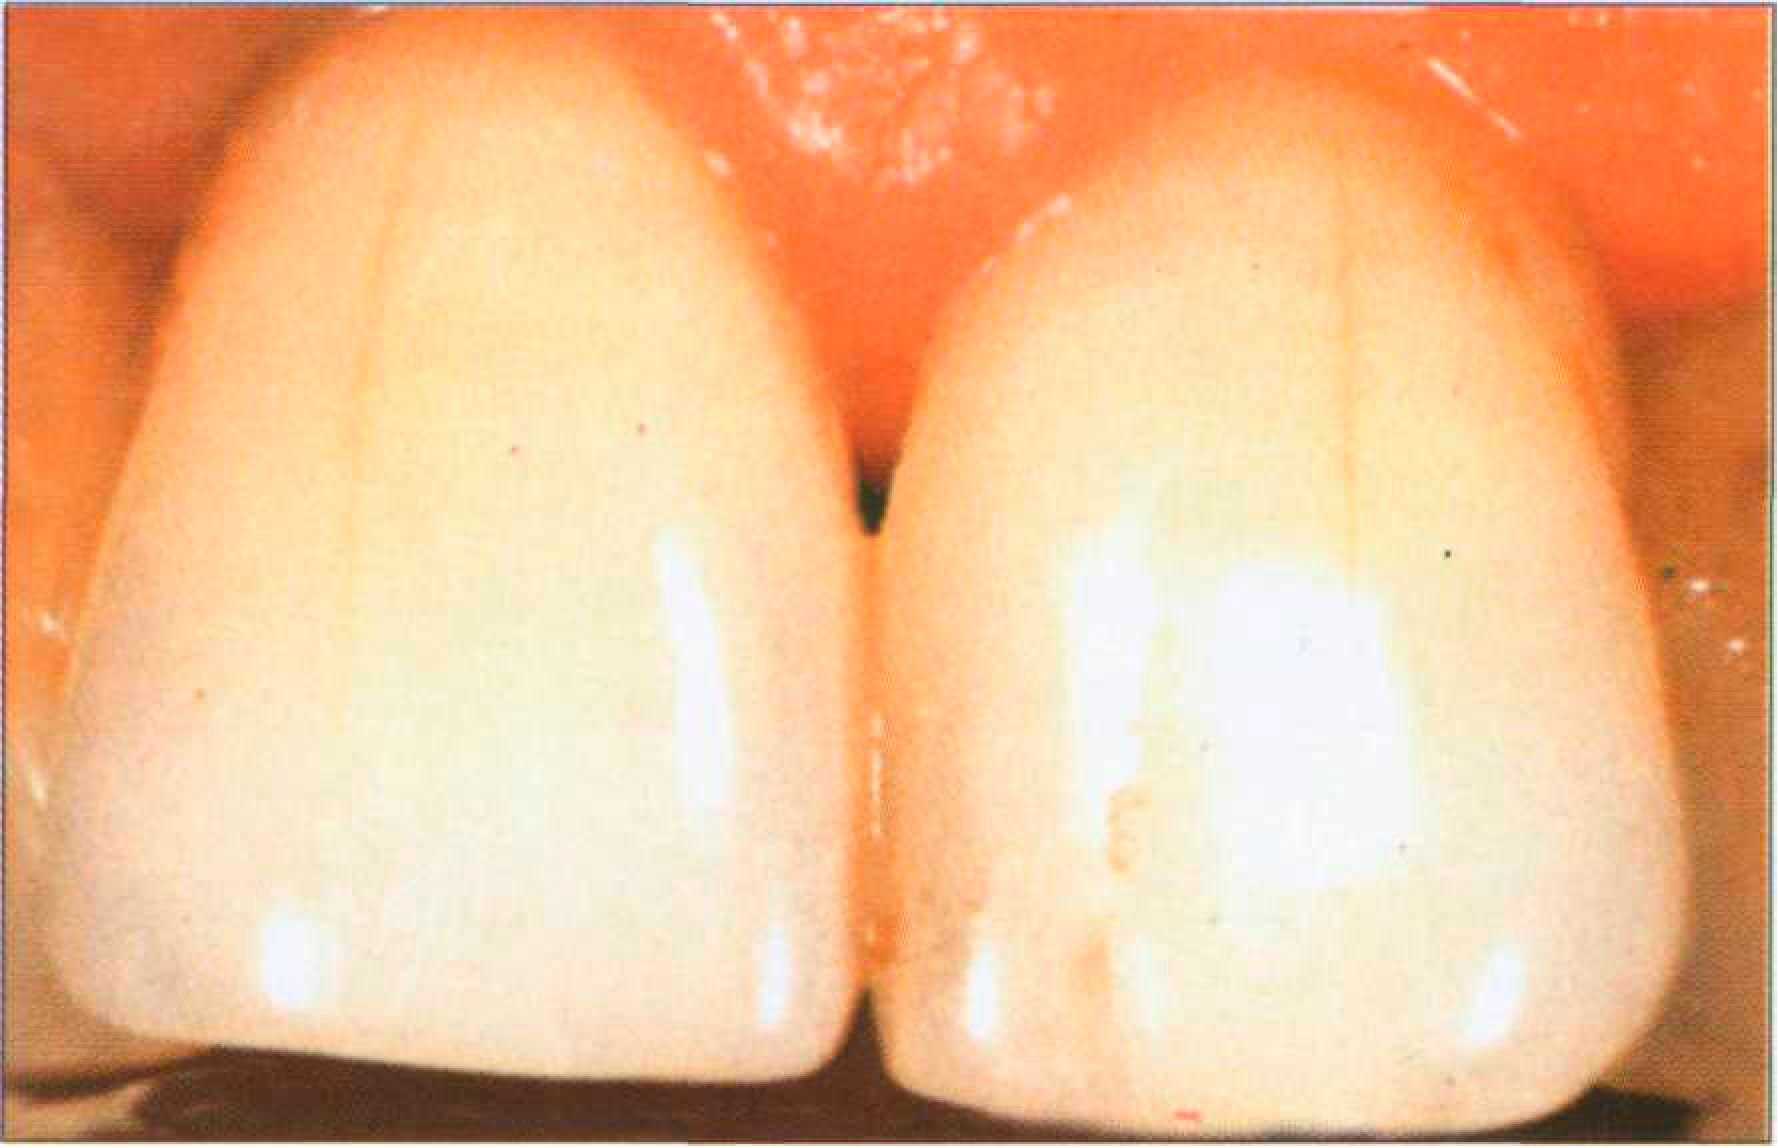

Значительное количество мягкого налета придает зубу белесоватый вид, особенно при высушивании. Однако по отношению к эмали мягкий налет является внешним образованием, не затрагивающим существенно структуры зуба. В ряде случаев отмечается окрашивание его пищевыми продуктами, напитками, лекарственными веществами. Так, экзогенная пигментация налета может наблюдаться после полоскания полости рта раствором перманганата калия. Появление на зубах зеленого налета свидетельствует о поражении пелликулы зуба, в которую внедряются хромогенные грибы. Существует мнение, что причиной зеленой окраски налета является хлорофилл, выделяемый микроорганизмами. Локальное нарушение окраски эмали и дентина. Локальные поверхностные поражения эмали под влиянием экзогенных воздействий в виде ограниченных пятен чаще всего возникают как результат очаговой подповерхностной деминерализации эмали при начальном кариесе и на ранних этапах кислотного некроза. Начальный кариес проявляется в виде белесоватого помутнения эмали — меловидного пятна. При высушивании зуба кариозный участок приобретает молочно-белый вид. |